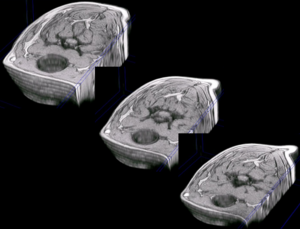

detalle de la columna vertebral cervical en una reconstrucción en 3D del cuello de un perro a partir de imágenes de resonancia magnética (secuencia GE) |

varias reconstrucciones del cuello del mismo paciente, a diferentes niveles |